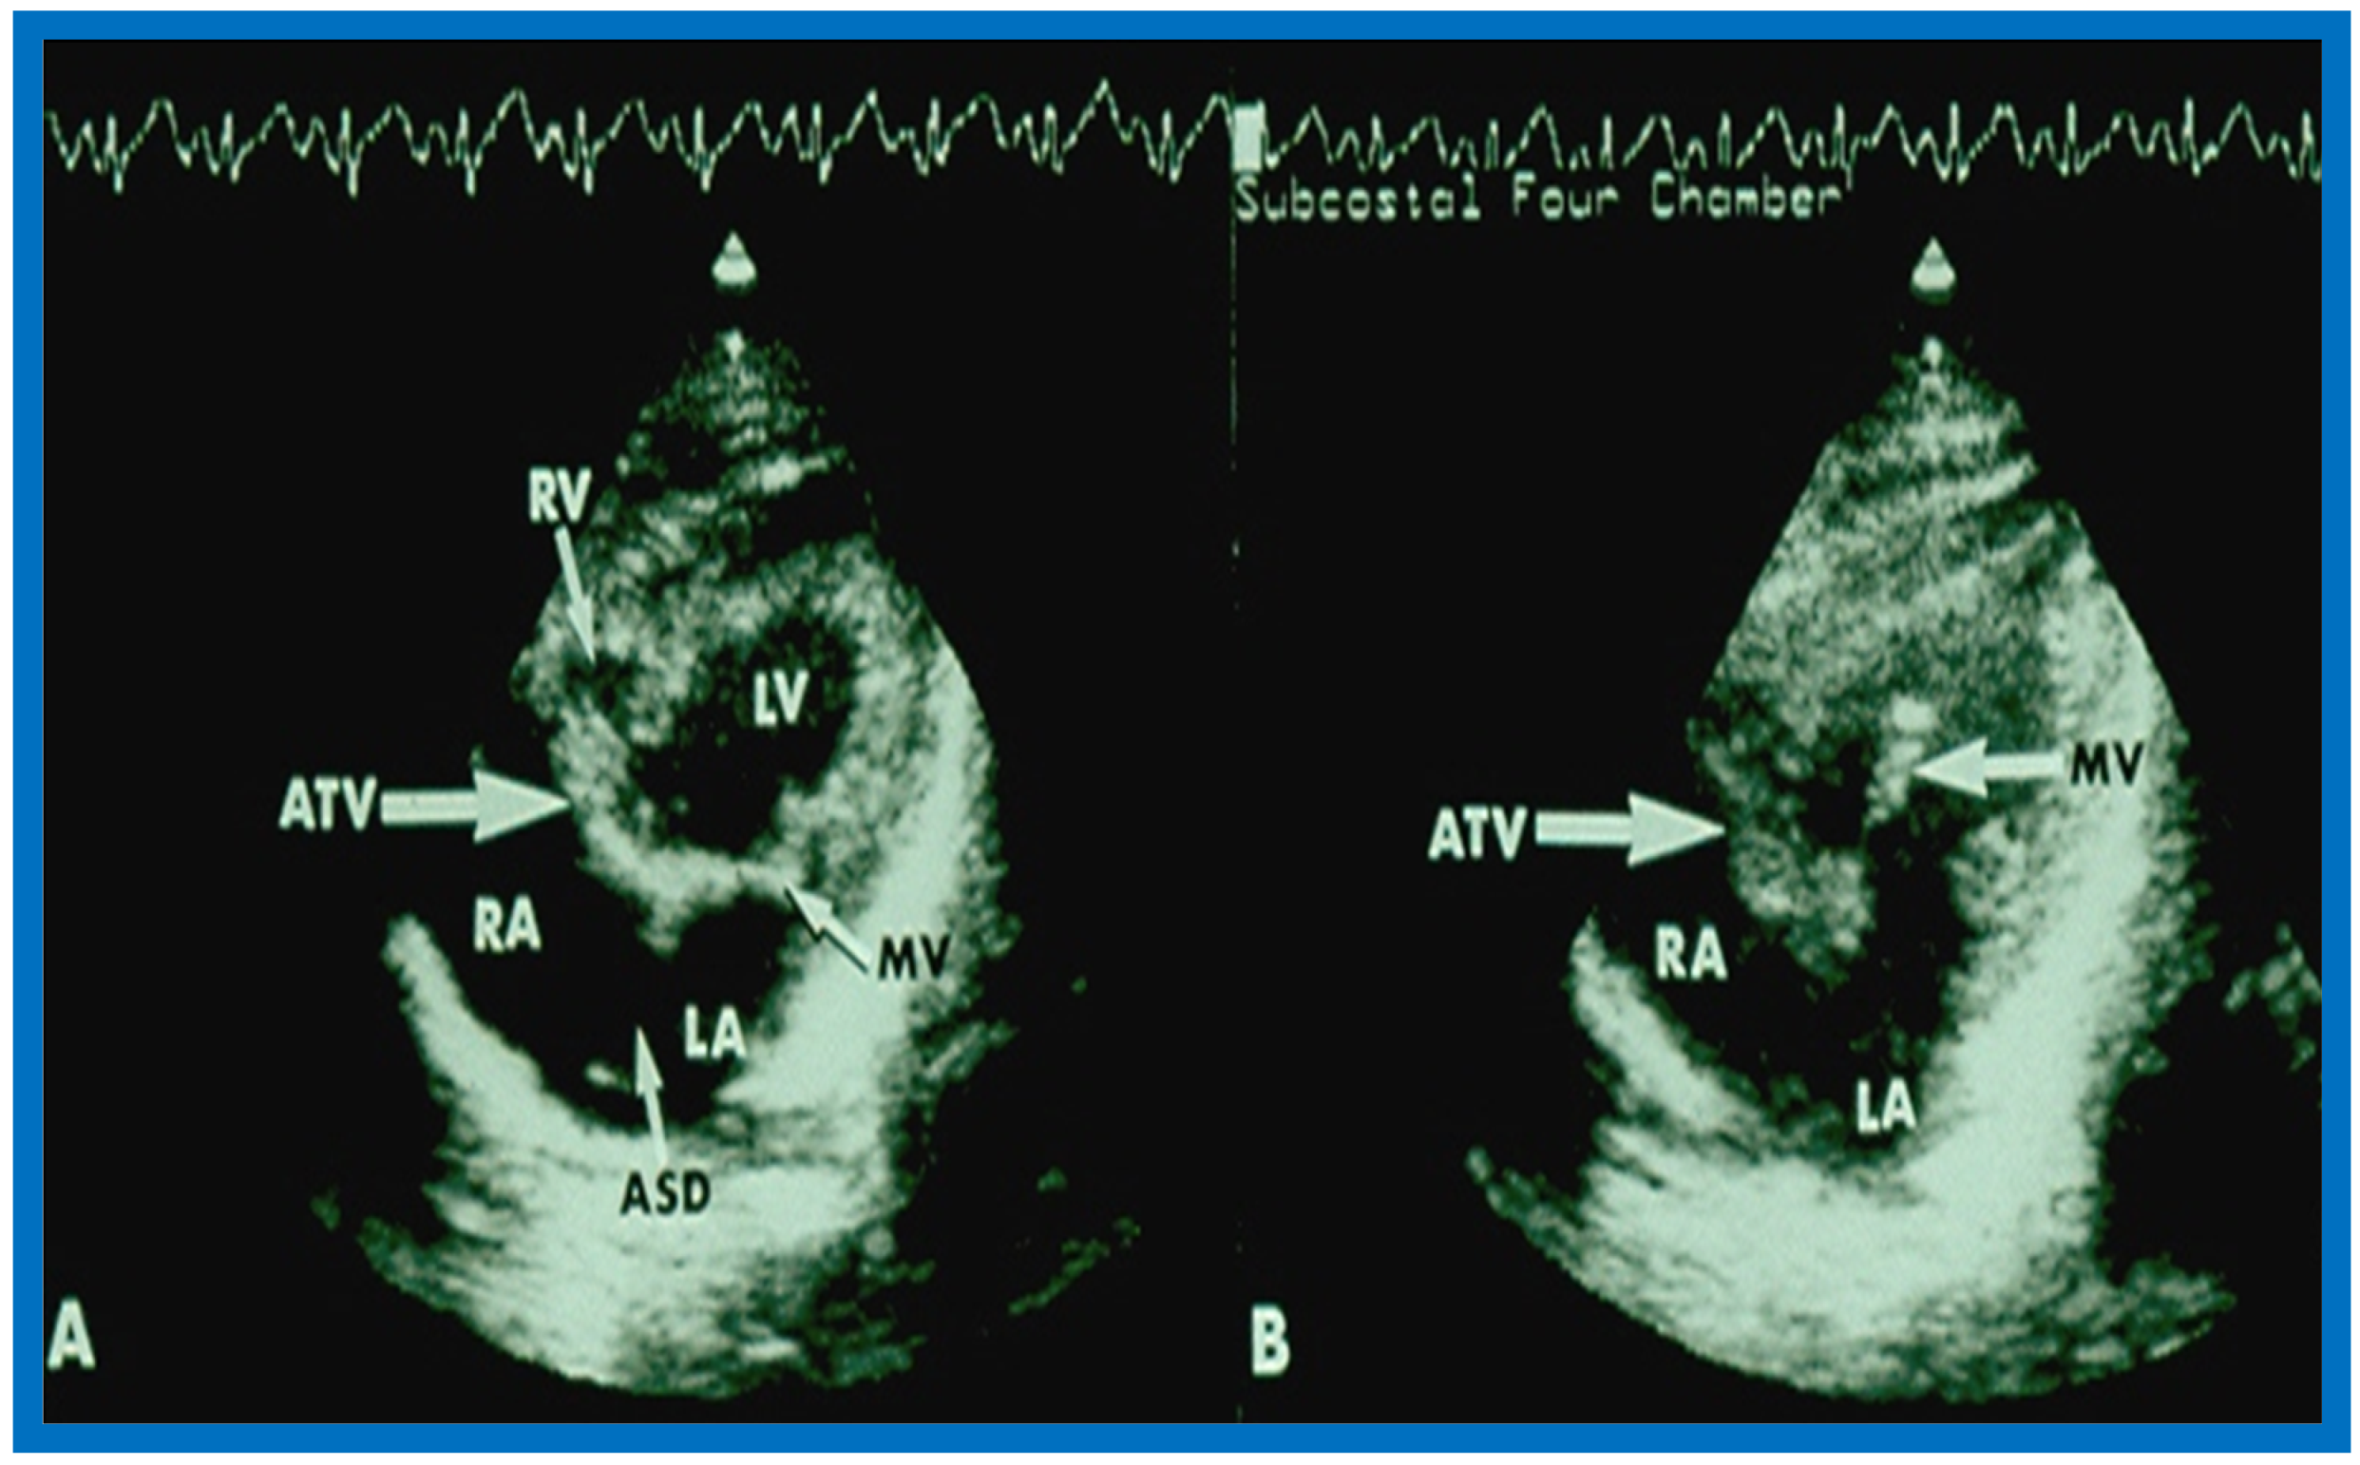

14. Echocardiographic Demonstration of Atrioventricular Type of Tricuspid Atresia

The author reported on the clinical, radiographic, ECG, echocardiographic and hemodynamic features of a rare case of common atrioventricular canal (currently called atrioventricular septal defect) mimicking tricuspid atresia in an eight-year-old child [15]. The clinical, radiographic and ECG characteristics were similar to those of classic tricuspid atresia. Hemodynamic data secured at cardiac catheterization were also similar to those seen with tricuspid atresia. A two-dimensional echocardiogram demonstrated an ostium primum atrial septal defect with a common atrioventricular valve and a small RV (Figure 50a,b); the entry into the RV appeared to be occluded by a leaflet of the common atrioventricular valve. Left ventricular cineangiogram in postero-anterior view demonstrated “gooseneck” deformity, similar to that seen in atrioventricular canal defects [15]. However, right atrial angiography resulted in direct emptying of the contrast material into the left ventricle via an ostium primum atrial septal defect (Figure 51). The floor of the right atrium seemed to be formed by a leaflet of the common atrioventricular valve (Figure 51). Thus, the two-dimensional echocardiographic and right atrial cineangiographic features appeared to be distinctive, and could be utilized to distinguish this anomaly from other varieties of tricuspid atresia.

Figure 50.

Selected two-dimensional, subcostal, four-chamber echocardiographic frames with an open (a) and closed (b) atrioventricular valve. Line drawings on the right of a and b are made for greater clarity and for labeling. A large ostium primum atrial septal defect (10 ASD) is shown in a. When the large atrioventricular valve leaflet is open (a), it completely closes the right ventricle (RV) from the right atrium (RA) and ventricular septal defect (VSD) and allows emptying of blood from both atria into the left ventricle (LV). When atrioventricular valve leaflet is closed (b), it continues to occlude the RV from the RA while allowing the VSD to freely communicate between RV and LV. Ap, Apex; AtTV, atretic tricuspid valve; Ba, base; L, left; LA, left atrium; R, right. Reproduced from Rao P.S. [15].

Figure 51.

Selected right atrial (RA) angiographic frame in postero-anterior view demonstrating that the floor of the right atrium is formed by one of the leaflets of the atrioventricular valve; this is marked by a large arrow. The contrast material exited the RA via an ostium primum atrial septal defect shown by small arrows with subsequent opacification of the left ventricle (LV). C, catheter; LA, left atrium. Reproduced from Rao P.S. [15].

The reported anomaly is definitely different from classic tricuspid atresia, but has physiologic effects similar to classic tricuspid atresia. A detailed review of the literature at that time suggested that this anomaly is extremely rare, with only one brief mention of a similar case by Van Praagh by that time [50]. Evaluation of crux cordis (Figure 54) on two-dimensional echocardiogram (subcostal four-chamber view) may help to distinguish these anomalies from each other. In muscular type of tricuspid atresia, a dense band of echoes is seen where the normal tricuspid valve should be (Figure 52a). In membranous types of tricuspid atresia, a thin membrane is seen instead (Figure 52b). In both types, the anterior leaflet of the detectable atrioventricular valve is attached to the left side of interatrial septum (Figure 52a,b). In the atrioventricular canal type of tricuspid atresia, the crux cordis is abnormal and cannot be identified, and a large atrioventricular valve leaflet occludes the entry of the RA into the RV (Figure 52c). It was concluded that two-dimensional echocardiographic and angiographic features help differentiate atrioventricular canal type of tricuspid atresia from classic tricuspid atresia cases [15].

Figure 52.

Line drawings demonstrating two dimensional echocardiographic appearances in subcostal four-chamber view of the muscular (a), membranous (b), and atrioventricular canal (c) variants of tricuspid atresia. (a) The atretic tricuspid valve is represented by a thick band of echoes between the right atrium (RA) and the small right ventricle (RV) in the muscular type. (b) The tricuspid valve is represented by a thin line in the membranous type. Note that crux of the heart (arrows in a and b) is well seen in both these types (a and b). The attachment of the anterior leaflet of the detectable atrioventricular valve to the left side of the interatrial septum is evident. (c) In the atrioventricular canal type of tricuspid atresia, the anterior leaflet of the detectable atrioventricular canal is attached to the anterior wall of the heart, occluding the right ventricle from the right atrium and allowing blood exit of both atria into the left ventricle (LV). Crux cordis and the atrioventricular portion of the interventricular septum are not seen. Reproduced from Rao P.S. [15,40].